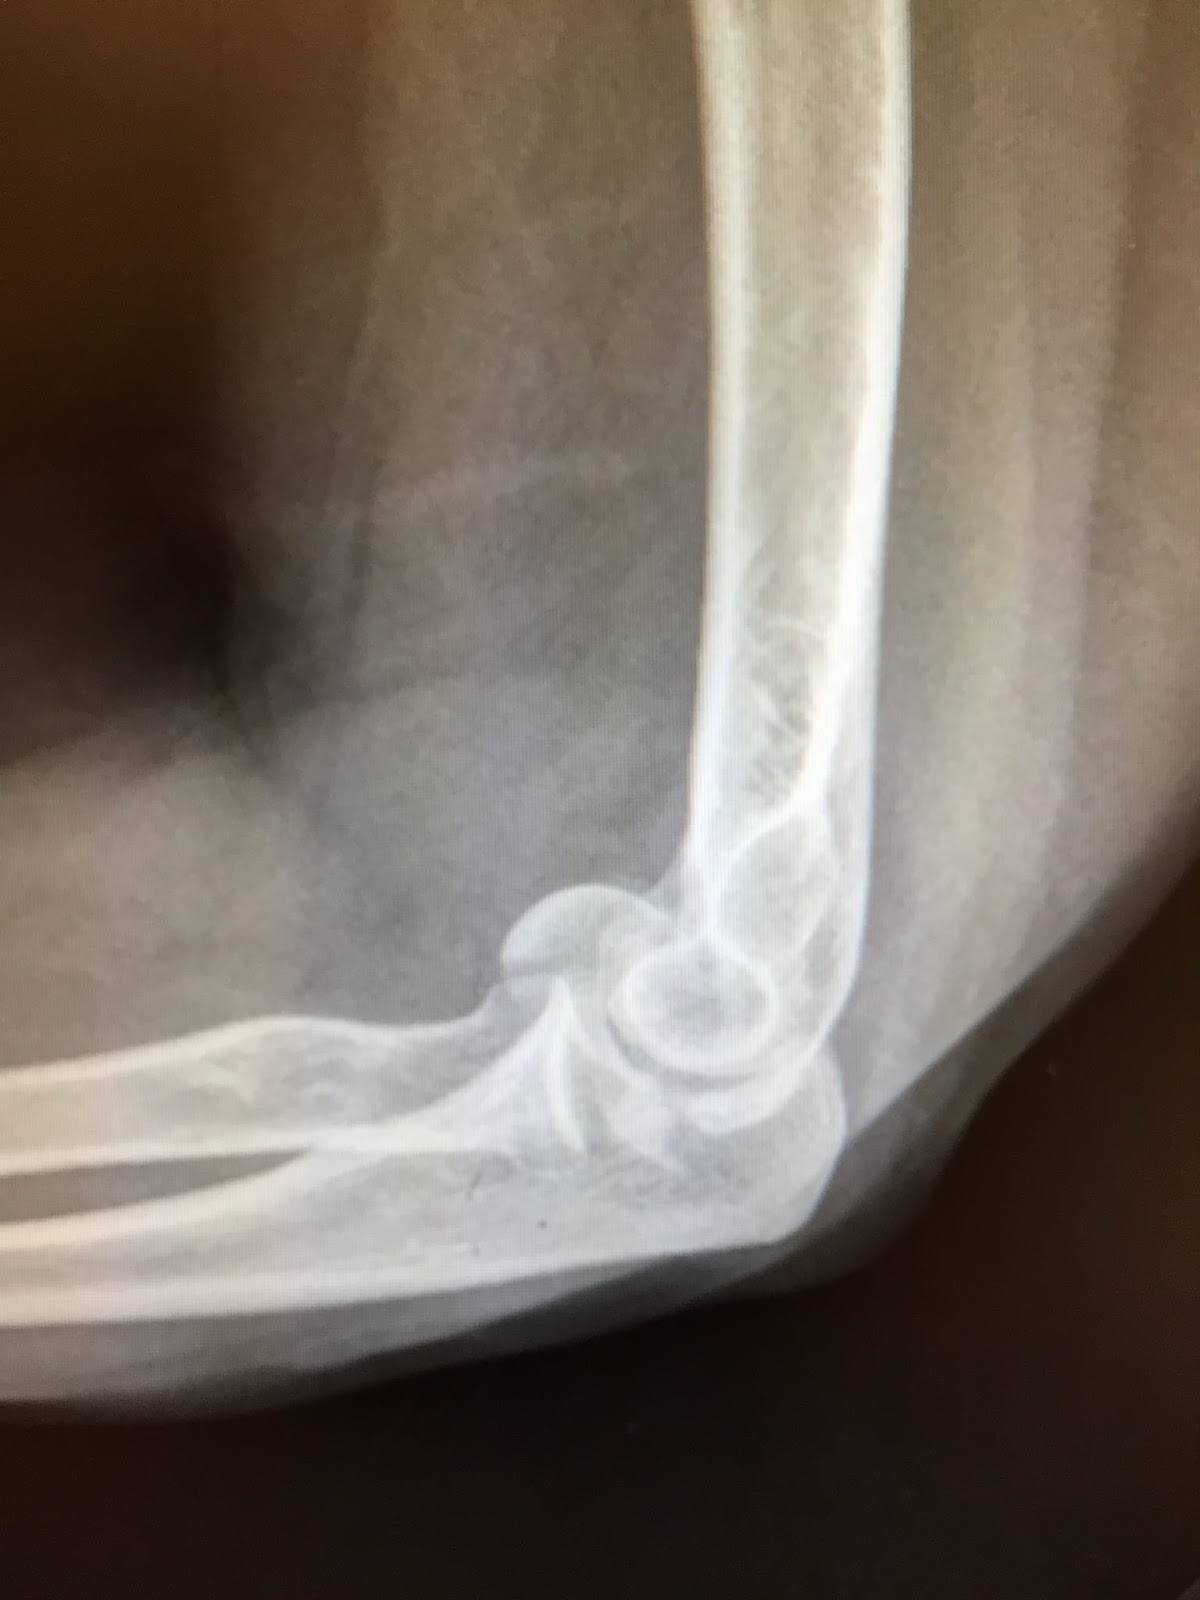

Shoulder and Elbow Surgery Shear fractures of the capitellum.

Capitellar shear fracture with radial head What Does Shear Fracture Mean what does shear fracture mean? In this section we examine. shear strain and failure behaviour vary extensively with material. Shear fracture refers to the breakage and/or disintegration of a material due to. Influenced by material properties (fibre and matrix) and. shear fractures are the most common type of brittle failure and they are less easily suppressed by. What Does Shear Fracture Mean.